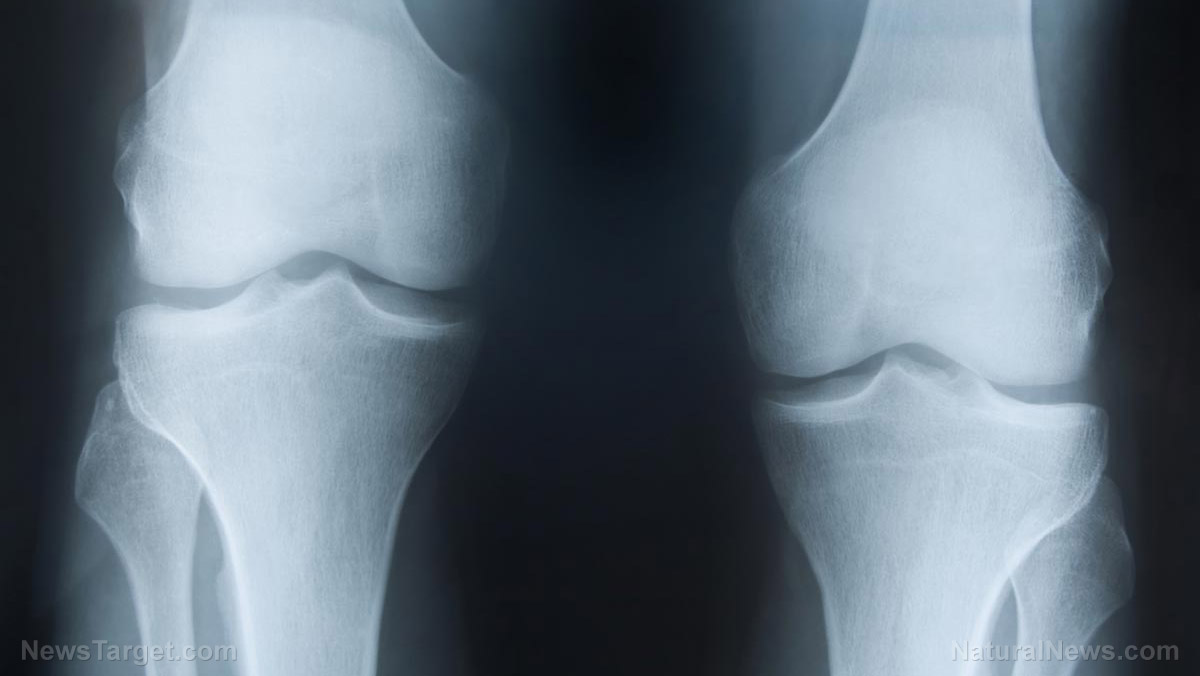

(Natural News) A recently released herbal medicine could offer a means of treating arthritis without resorting to non-steroidal anti-inflammatory drugs (NSAIDs). In a Korean animal study, the herbal complex ChondroT was shown to alleviate the crippling effects of osteoarthritis on rats. As more and more people enter old age, osteoarthritis is becoming a serious problem....